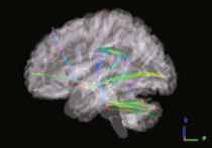

«Изменения коннектома головного мозга у пациентов с детским церебральным параличом в поздней резидуальной стадии при транслингвальной нейростимуляции». Обобщена МР-семиотика структурных и функциональных изменений головного мозга у детей со спастической диплегией. У детей с ДЦП в поздней резидуальной стадии преобладает снижение коннективности между компонентами сети выявления значимости и корой лобно-теменной области, компоненты которой также структурно связаны с компонентами сенсомоторной сети. При выполнении коннектометрического анализа трактов после ТЛНС (основная группа) выявлено повышение фракционной анизотропии более чем на 20 % (p < 0,001) в передней спайке (47 % от общего количества волокон), правом нижнем лобно-затылочном пучке (13 % волокон), левой поясной извилине (10 % волокон), правой зрительной лучистости (6,7 % волокон), мозолистом теле (6 % волокон), правой поясной извилине (1,3 %) (рисунок).

| Графическое представление результатов межгруппового статистического анализа: 2D-реконструкция проводящих путей белого вещества головного мозга с повышением ФА после ТЛНС в аксиальной (а), сагиттальной (б) и корональной (в) плоскостях. Показаны проводящие пути и часть их волокон, которые повысили ФА более чем на 20 % после комплексной реабилитации | ||

При выполнении коннектометрического анализа трактов после стандартной двигательной реабилитации (группа сравнении) статистически значимого повышения фракционной анизотропии (более чем на 20 %) не выявлено. При проведении диффузионной МРТ у детей с ДЦП в поздней резидуальной стадии выявлено статистически значимое снижение фракционной анизотропии в трактах белого вещества головного мозга, что свидетельствует о нарушении общих процессов миелинизации и, следовательно, скорости проведения нервных импульсов по их аксонам. Выявлены структурные и функциональные изменения головного мозга у пациентов с ДЦП после ТЛНС, которые свидетельствуют об усилении активации процессов нейропластичности.